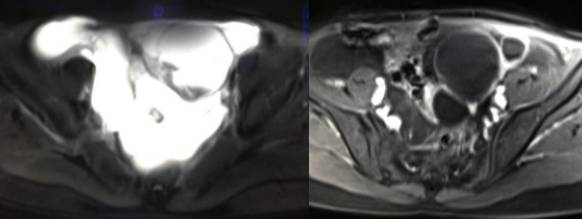

MR检查:

病理结果:黄体血肿

根据时间不同MR信号也有所不同,TIWI脂肪抑制序列可以鉴别脂肪和出血。

巧克力囊肿:常呈多发的单囊或多囊改变,病灶大小不等,囊壁厚薄不均,囊内信号复杂,囊内或各囊腔间血液因出血时期不同,信号常呈多样性,囊肿内反复出血、破裂,形成相互粘连的多房性囊肿,是其较为特征性的表现。

在鉴别卵巢畸胎瘤、出血性囊肿或巧克力囊肿时,MR 脂肪抑制T1WI 可明确肿块内高信号成分是脂肪还是出血,同时由于脂肪组织与非脂肪组织的共振频率不同,在两者交界处沿磁场频率编码方向出现化学位移伪影,但出血性囊肿与巧克力囊肿的鉴别有时较为困难。

囊腺瘤与囊腺癌的鉴别要点

囊腺瘤的MR 特点 :

(1) 单侧、单房、囊性多见;

(2) 肿瘤壁多菲薄,厚度<3 mm,且厚薄较均匀,与周围组织分界清楚;(3)肿瘤间杂有细条状及少许附壁乳头状突起,边界多较清楚,信号较一致;(4)腹水少见。

囊性卵巢癌的MR 特点 :

(1)双侧,以囊实性居多;

(2) 肿瘤形态多样、不规则,内部结构混杂并有明显强化;

(3)瘤壁厚度多> 3 mm,呈菜花状、结节状突起,与周围组织界限不清;(4)腹水与腹膜转移灶多见。